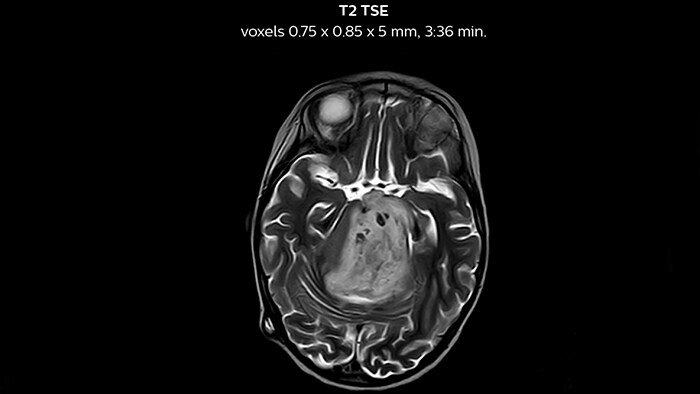

Ultimate precision at maximum speed with Dual AI

Take the leap forward with SmartSpeed Precise, the next generation acceleration technique that expands the proven Compressed SENSE and SmartSpeed technologies with a unique integrated Dual AI innovation, providing ultimate precision at maxiumum speed.

Clinical cases from nearly every anatomy

Explore 200+ clinical cases and download exam cards from peers around the globe, showcasing how Philips MR technology enhances your imaging capabilities.